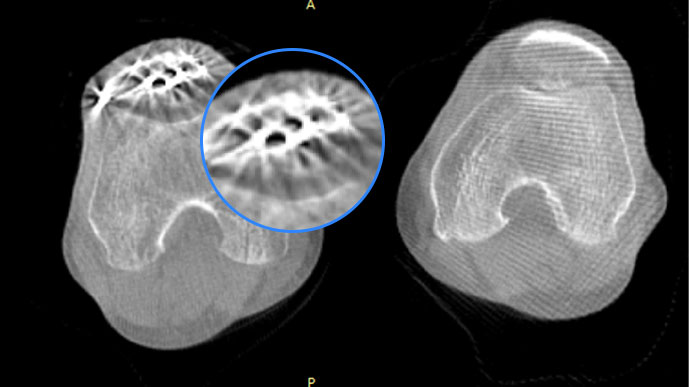

智能金属伪影抑制算法

关闭金属伪影校正

开启金属伪影校正